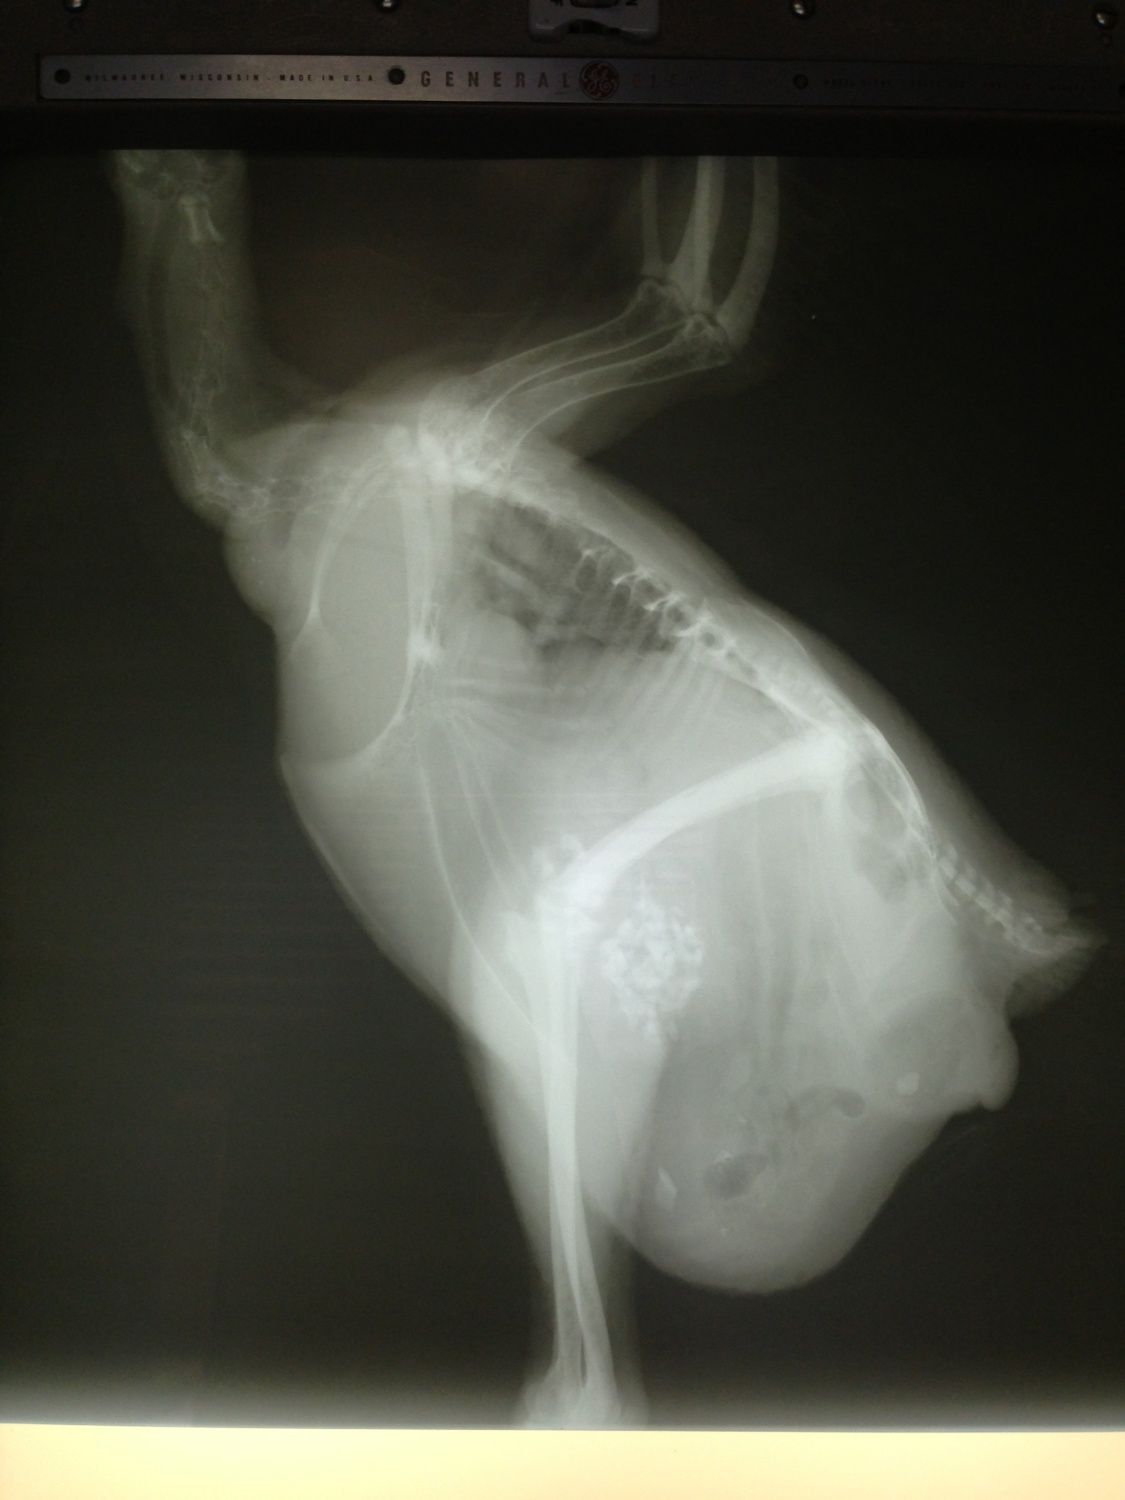

I just wanted to share and ask for thoughts and prayers if you are willing, for my Maxine. I thought she was egg bound, but she ended up laying an egg right before we headed out to the vet. She is swollen below her vent. Eating and drinking and acting normally. We had x-rays and she is staying the night for barium enema studies and blood work.

We are just waiting to hear what the barium study shows. I love this girl so much!!!